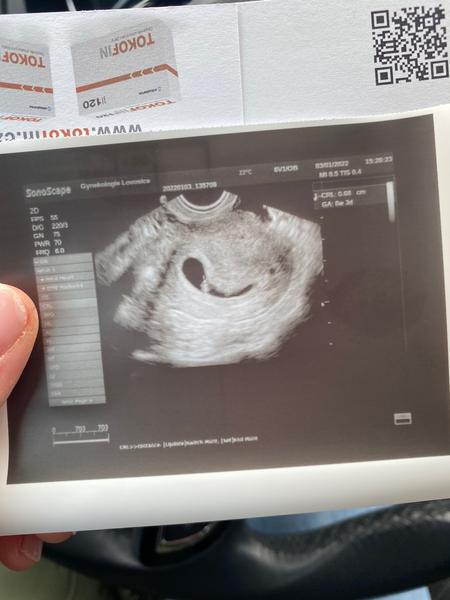

@katanovobran tak my dneska 6mm a srdíčko tluče a hematom je prý pryč 😍

@petradt1986 a v 5+5 jsem měla jen gestacni 7mm a můj dr mě poslal do nemocnice že to vidí spíše na mimoděložní. V 6+0 byl stále jen gestacni a v 7+0 bylo srdíčko a embryo 3,6mm. Dneska 7+3 embryo 6mm a můj dr už to vidí docela optimisticky... Ale jsem o týden pozadu dle utz. A v 5+5 jsem měla na utz vidět min než ty 🍀🍀🍀

Ahoj holky tak ja dnes byla u dr. Dle MS pry podle dr. 6+4tt (me teda vychazi 6+6tt ) nevim jak to počítá. Ale prte odpovida 5-6 tt. Je to v poradku? 4mm s embryonálním polem a srdecni akci. Tak snad to bude ok.

@petradt1986 tak já jsem dnes po uzv. Dle uzv 8+1, dle MS 8+6. Srdíčko jede hezky, malý vytahlo na 18mm